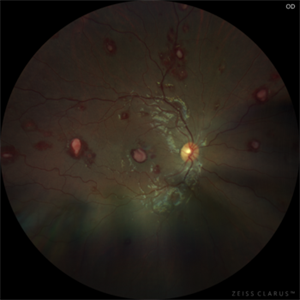

Leukemic Retinopathy - OD Leukemic Retinopathy - ODAug 1 2023 by Shaleen Arora A 14-year-old female was transferred from an outside hospital with a new diagnosis of B-ALL and WBC of 667,000. Following lumbar puncture, she developed blurry vision and floaters but denied curtaining, flashes, and diplopia. Ophthalmology was consulted to assess for disc edema. Exam revealed visual acuity of 20/100 OD and 20/200 OS. Imaging showed diffuse hemorrhages and Roth spots OU, consistent with leukemic retinopathy. The patient was followed by retinal specialists with spontaneous improvement in visual acuity over three weeks. Photographer: Camilo Martinez, Childrens National Medical Center, Department of Ophthalmology Condition/keywords: leukemia, leukemic infiltration, retinopathy, Roth spots

Leukemic Retinopathy - OS Leukemic Retinopathy - OSAug 1 2023 by Shaleen Arora A 14-year-old female was transferred from an outside hospital with a new diagnosis of B-ALL and WBC of 667,000. Following lumbar puncture, she developed blurry vision and floaters but denied curtaining, flashes, and diplopia. Ophthalmology was consulted to assess for disc edema. Exam revealed visual acuity of 20/100 OD and 20/200 OS. Imaging showed diffuse hemorrhages and Roth spots OU, consistent with leukemic retinopathy. The patient was followed by retinal specialists with spontaneous improvement in visual acuity over three weeks. Photographer: Camilo Martinez, Childrens National Medical Center, Department of Ophthalmology Condition/keywords: leukemia, leukemic infiltration, retinopathy, Roth spots